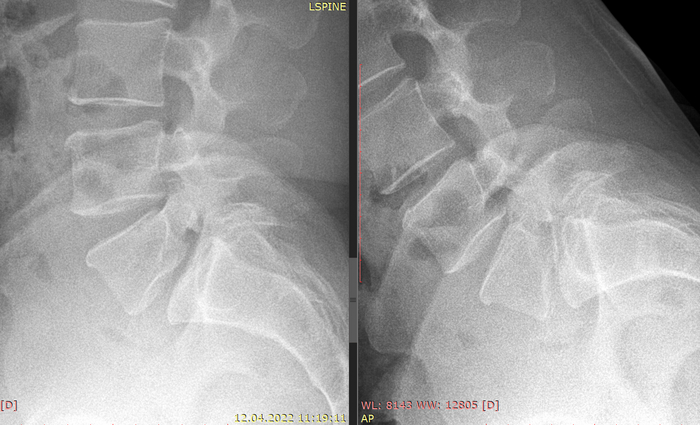

Делаем рентген, смотрим улику № 2.

Имеется несращение кости (дужки). Это аномалия развития, которая называется Spina bifida.

Смотрим сбоку.

Верхняя стрелка - нормальная дужка.

Нижняя - несращение дужки и соответственно смещение позвонка.

При сгибании и разгибании оцениваем степень нестабильности.

Степень нестабильности небольшая, менее 25% длины тела позвонка. Это означает что пока что можно полечиться консервативно.